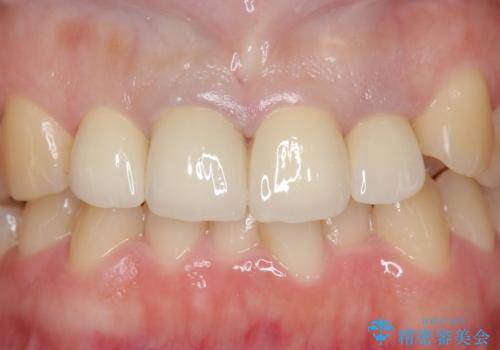

見た目改善のため、前歯4本をオールセラミッククラウン(スペシャル)で補綴しました。

前歯の補綴ではオールセラミッククラウンを希望される患者様が多いですが、オールセラミッククラウンの中でも、エコノミー、スタンダード、スペシャル、エクセレントとランクがあります。

その中でも特に審美性が高いのがスペシャル、エクセレントです。スペシャル、エクセレントは口腔内写真をもとに熟練の技工士が、患者様の口腔内に合わせたオーダーメイドのクラウンを製作致します。